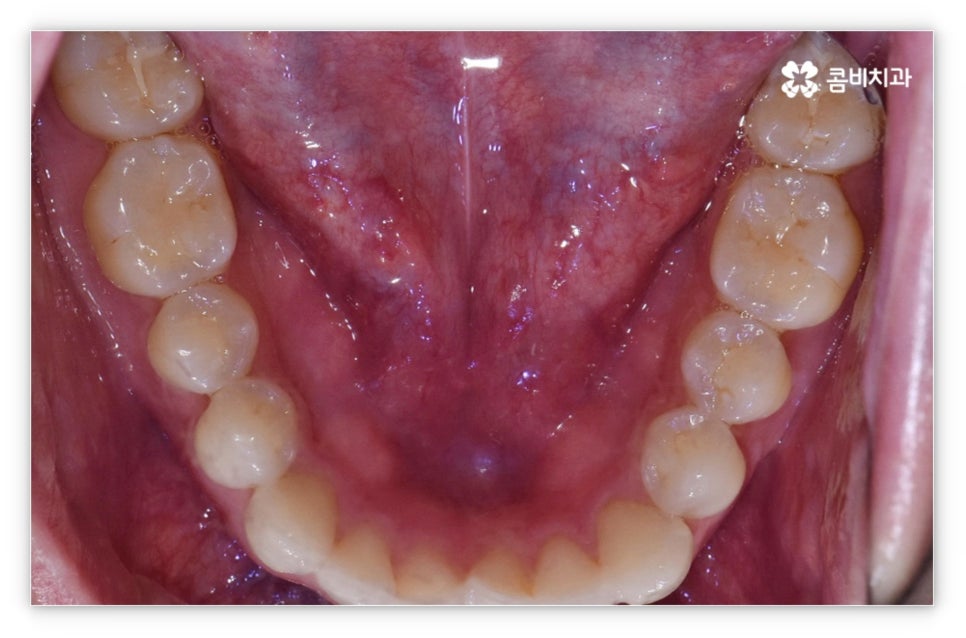

살펴본 바와 같이 앞니설측교정 의 장점에도 불구하고 아랫니 부분은 장치가 혀에 닿게 되기 때문에 환자분들께서 불편함을 느낄 수 있고 혹시라도 혀가 브라켓에 잘못 쓸리거나 눌렸을 때 통증이 발생할 수도 있으며 발음이 불분명해지는 문제가 생길 수 있는데요. 이러한 이유로 앞니설측교정 에 대해서 고민이 되시는 분들은 윗니 부분은 설측으로, 아랫니 부분은 일반 교정처럼 순측으로 진행하는 콤비 교정에 대해서 알아보시면 좋을 거예요. 위의 사진에서 살펴보실 수 있는 경우가 바로 이렇게 콤비 교정으로 진행한 환자분의 케이스인데 아랫니의 경우 보통 입술에 가려 별로 드러나지 않는 데다가 치아 색상인 세라믹 재질로 된 브라켓을 이용하기 때문에 설측 교정과 비교해도 심미성이 크게 떨어지지 않는다는 것을 알 수 있어요. 콤비 교정의 경우 설측 교정보다 비용적인 부담도 줄일 수 있으니 각 장치에 대한 장단점을 의료진분들과 충분히 상담하셔서 자신에게 맞는 장치를 선택하시면 좋을 거예요.